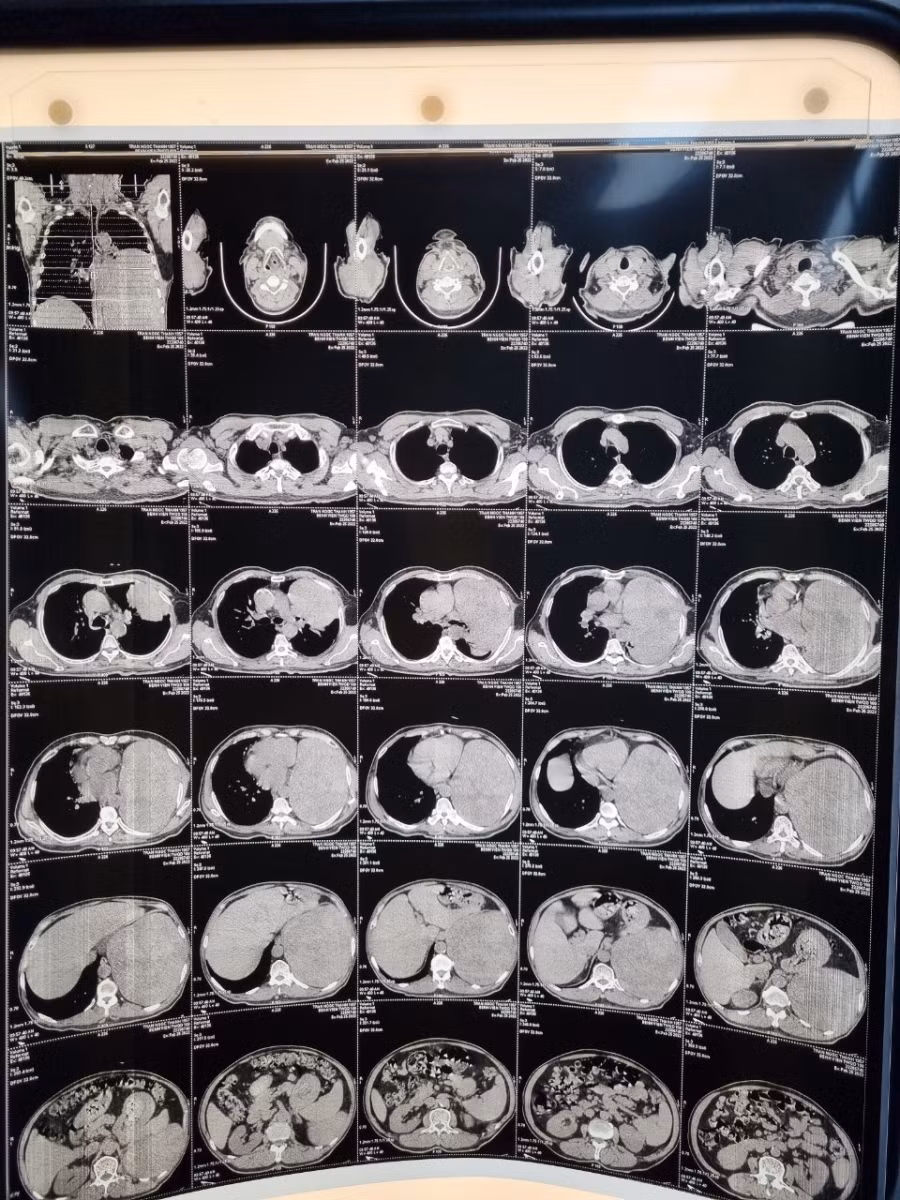

Phim chụp CLVT cho thấy khối u có kích thước lớn. Nguồn: BV 108.

Trên phim chụp CLVT cho thấy: một khối u đặc, khổng lồ, chiếm 2/3 dưới của lồng ngực bên trái, ranh giới tương đối rõ. Sinh thiết xuyên thành kết quả lành tính.

Căn cứ vào hình ảnh, xét nghiệm và khám lâm sàng các bác sĩ chẩn đoán đây là khối u xơ màng phổi đơn độc khổng lồ. Đây là bệnh lý vô cùng hiếm gặp.